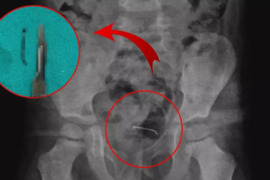

5 yaşlı uşağın bədənində metal əşya aşkar edilib

Bitlisin Güroymak rayonunda 5 yaşlı uşaq 9 ay əvvəl səhvən sancaq udub. Daha əvvəl udma şikayəti ilə tibbi müəssisələrə müraciət edən və heç bir nəticə ala bilməyən 5 yaşlı uşağın ailəsi sonuncu dəfə 4 gün əvvəl Tatvan Dövlət Xəstəxanasına müraciət edib. türk mediyasına istinadən xəbər verir ki, qarı